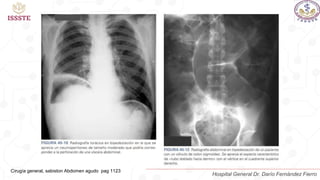

PRUEBAS DE IMAGEN

Radiografía de abdomen de dos posiciones (decúbito y bipedestación